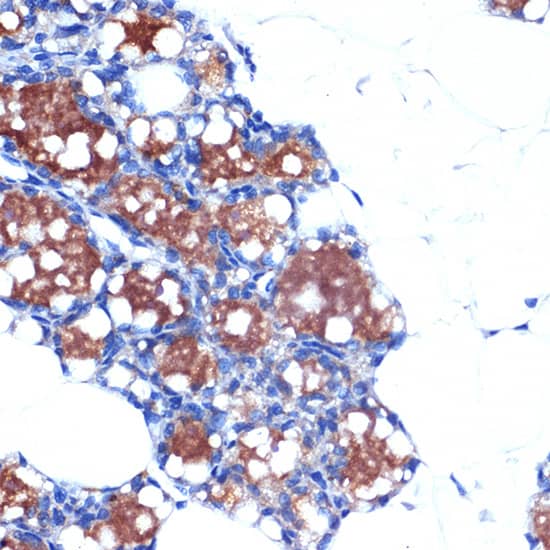

UCP1/3 Antibody (0S10O10)

NBP3-33199

Species:

Mu, Rt

Applications:

WB, ELISA, ICC/IF, IHC

Host:

Rabbit Monoclonal